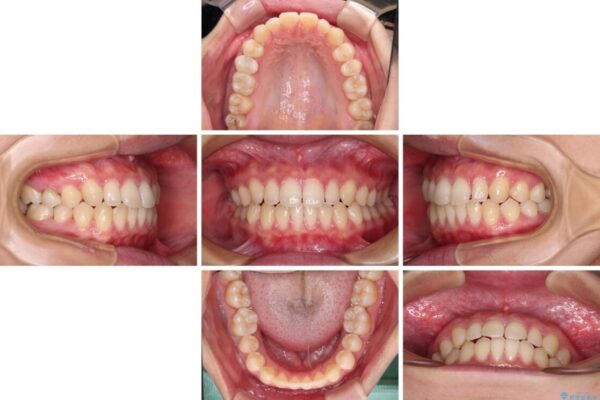

治療前

• 隙間だらけの歯列 インビザラインで改善 治療前画像

治療後

• 隙間だらけの歯列 インビザラインで改善 治療後画像